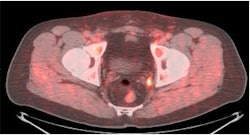

| PET/CT with anti-F-18 FACBC (below) shows left obturator lymph node better than CT (top) and PET (above) images alone. |

Another research study being presented at the SNM conference this week involves a new molecular imaging agent that could improve the diagnosis of recurrent prostate cancer and determine the best possible course of treatment for patients.

The agent, developed by Mark Goodman, MD, at Emory University in Atlanta, consists of a fluorine-based radioisotope paired with a synthetic amino-acid analog similar to the naturally occurring amino acid L-leucine (anti-F-18 FACBC).

Not only was the agent shown to be highly accurate in differentiating recurrent tumors in the prostate from metastatic cancer, but researchers believe the agent could help change patient treatment and improve the prognosis for prostate cancer patients.